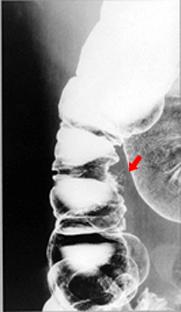

A resected case of diverticulal abscess of the ascending colon.

Diverticulum/Diverticulitis, Peridiverticular Abscess

Location

Large intestine(Colon)/Ascending colon

Technique, Method

X-ray

Size

20 - 24